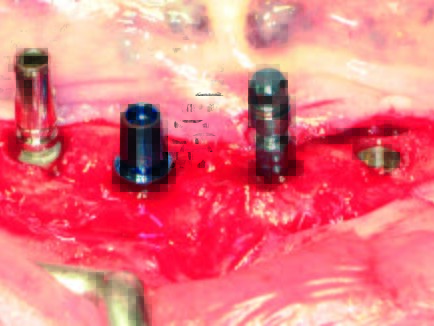

In Rahmen einer Fortbildungsveranstaltung wurde einem zahnlosen 81-jährigen Patienten (Abb. 8) mit geeigneter Indikation angeboten, das SynCone-Prinzip und die Anwendung des ATLANTIS Conus-Abutmentskonzepts kennenzulernen und damit den Fortbildungsteilnehmern Einblick in die direkte Anwendung zu ermöglichen (Abb. 9). Es erfolgte zunächst eine Duplierung der Unterkieferprothese als röntgenopake Bariumsulfatprothese. Nach der 3D-Planung (Abb. 10) und Herstellung einer gedruckten 3D-Schablone erfolgte der operative Eingriff in Lokalanästhesie unter intravenöser Single-Shot-Gabe des Antibiotikums Clindamycin 600 mg. Folgende Implantatsysteme kamen (von links nach rechts) zur Anwendung: Astra Tech EV (OsseoSpeed, Länge 13 mm, Ø 4,2 mm in regio 034), Straumann Bone Level (Länge 12 mm, Ø 4,1 mm in regio 32), Xive S (Länge 13 mm, Ø 4,5 mm in regio 42) und ANKYLOS C/X (C Länge 11 mm, Ø 5,5 mm regio 044). Die Bohrschablone wurde mit mehreren Osteosynthese-Schrauben auf ihrem Lager fixiert (Abb. 11). In typischer Art und Weise wurden die verschiedenen Implantate nach den Vorgaben ihrer Bohrprotokolle inseriert (Abb. 12-14).

Nach Wundverschluss und einer Einheilphase von drei Monaten erfolgte die chirurgische Implantatfreilegung. Nach Entfernung sämtlicher Verschlusskappen wurden die entsprechenden Gingiva- oder Sulkusformer eingebracht (Abb. 15, 16). Zuvor wurde die Abformung⁴ (Abb. 17) mit einem A-Silikon in mittlerer Konsistenz für die Doppelmischtechnik in Kartuschen durchgeführt. Die einzelnen Abformpfosten wurden hierbei mit Pattern Resin LS in typischer Art und Weise verblockt, wie es in der Implantologie vielfach empfohlen wird⁵. Im nächsten Schritt erfolgte noch eine Vestibulumplastik zur Verbreiterung der Zone der Attached Gingiva. Parallel wurde im zahntechnischen Labor ein Meistermodell mit Zahnfleischmaske erstellt. Dort wurden das Meistermodell als auch die bestehende Unterkieferprothese des Patienten digitalisiert. Die gematchten Daten wurden an das ATLANTIS-Fertigungszentrum versandt. Auf der webbasierten Plattform ATLANTIS WebOrder wurden die patientenspezifischen Daten angelegt und vier individuelle Abutments bestellt. Zudem wurden die Art der gewünschten Restauration und das Material für den vorliegenden Patientenfall bestimmt: ATLANTIS Conus-Abutment Overdenture 5 Grad und Titan. Wenige Tage nach dem Versand der Daten wurde ein Designvorschlag für die konischen Abutments zugestellt, der im 3DEditor begutachtet und bis zu einem gewissen Grad bearbeitet werden kann. In der Maske des 3D-Editors können die Länge der Conus-Abutments (Margin Height), die mesial-distale Achse (MD Angle) sowie die fazial-linguale Achse (FL Angle) geändert werden. Die virtuelle Konstruktion der Abutments kann am Monitor in vielen verschiedenen Ebenen und Ausrichtungen begutachtet werden. Von Vorteil ist unter anderem, dass das Behandlungsteam das Set-Up (hier: die gescannte und vorhandene Prothese) einblenden und somit die Abutments in Bezug auf die angestrebte prothetische Versorgung beurteilen kann. In diesem Fall waren keine Änderungen notwendig. Nach Freigabe der Konstruktion wurden die ATLANTIS Conus-Abutments in Titan umgesetzt⁶.

Die ATLANTIS Conus-Abutments, die zugleich als industriell gefräste Primärteile dienen sollten, sowie der zugehörige Einbringschlüssel wurden versandt. Die vier Conus-Abutments wurden unter Zuhilfenahme des Einbringschlüssels inseriert (Abb. 18). Es zeigte sich eine ausgezeichnete Parallelität. Danach wurden die Abutments implantatspezifisch (Astra Tech OsseoSpeed Abb. 14: Die vier verschiedenen Implantate in situ mit ihren jeweiligen Verschlusskappen. Abb. 15: Gingiva oder Sulkusformer. Abb. 16: Gingiva- oder Sulkusformer in situ. EV mit 25 Ncm, Straumann mit 35 Ncm, ANKYLOS mit 15 Ncm, Xive mit 24 Ncm) definitiv angezogen (Abb. 19). Abschließend erfolgte eine abschließende radiologische Kontrolle (Abb. 20). Die ANKYLOS Konuskappe Degulor für SynCone 5° wurden dem Patienten mitgegeben. Der überweisende Zahnarzt war in die Planung und Gestaltung der Endversorgung von Anfang an mit Abteilungsleieinbezogen. Seitens der Autoren wurde die Einpolymerisierung der Konuskappen (Abb. 20) in die vorhandene Prothese allein aus wirtschaftlichen Erwägungen angeraten.